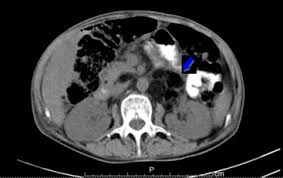

Tropheryma Whipplei An Unusual Cause Of The Accumulation In Positron Emission Tomography Clinical Microbiology And Infection